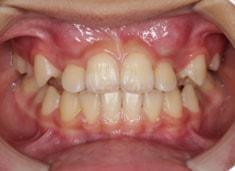

治療前

FX(フェイシャルアキシス)は85度なので東洋人の平均値に近く、下顎が前方に過剰成長するリスクは強くはありません。

しかしやはり上顎は劣成長で、下顎が優位な状態ではあります。

上下顎のギャップはありますが、顔面自体の幅径は良好な値を示していますので、スペース不足は拡大することによって解決できポテンシャルはあると考えられます。

左右の非対称もさほど強くありません。